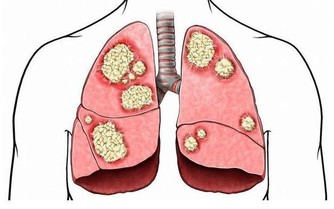

大腸癌多見於40歲以上的中年人,發生在兒童則十分少見。由於結腸癌起病較隱匿,早期癥狀不明顯,且無特異性,加之人們不易想到兒童能患結腸癌,往往易誤診為其他疾病。所以兒童結腸癌易延誤診斷,就診時常屬晚期,且常並發腸梗阻,預後較差。

目前大腸癌的成因仍然是未知之數,根據統計,和人們的飲食習慣有關,高動物性脂肪、高蛋白質和低纖維的飲食習慣有可能增加罹患腸癌的危險。

目前大腸癌的治療,以手術切除為最主要的方法,只要早期發現,早期手術切除乾淨,預後很好。化學治療與放射線治療是輔助治療,通常用來減少復發或減輕症狀